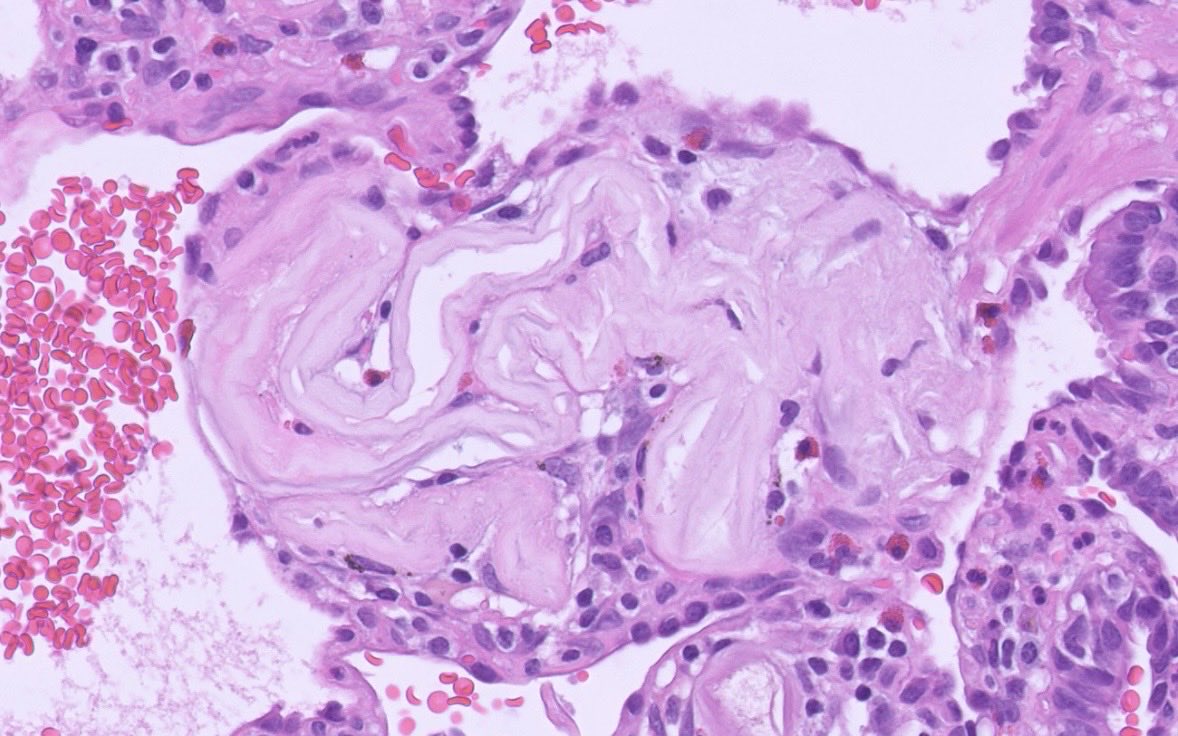

From a cancer resection. Does anyone know the mechanism by which these lesions form? (It’s a male, so not b9 metastasizing leiomyoma). #pulmonarypath #lungpath #thoracicpath #pathtwitter #pathx

PeterKobalka's tweet image. From a cancer resection.  Does anyone know the mechanism by which these lesions form? (It’s a male, so not b9 metastasizing leiomyoma). #pulmonarypath #lungpath #thoracicpath #pathtwitter #pathx